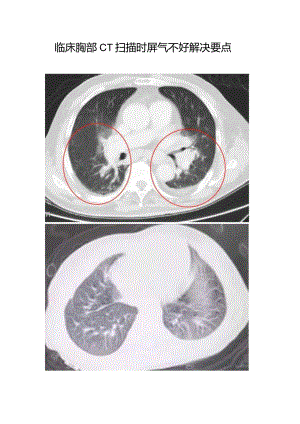

临床胸部CT扫描时屏气不好解决要点但是满足诊断的图像是:对于确实急危重患者需要的是紧急完成检查,而对于屏气时间短的一些老年患者如何处理呢,在胸部CT扫描中,老年患者有很大一部分,而且病变一般也多见,只有图像质量好才利于疾病诊断。屏气不好患者扫描1、屏气时间短的患者在常规胸部CT扫描中,扫描的方向为头侧向足侧,如下图:对于像老年人等屏气时间短的患者,可以颠倒顺序,采用足侧向头侧扫描,如下图:对于屏气时间短的患者,因为在训练呼吸时,患者可以进行屏气,但是时间短,如果我们从头侧向足侧扫,扫到肺底膈肌位置时已经正常呼吸了,这时候膈肌正常运动,导致肺底部出现呼吸运动伪影。而采用足侧向头侧的扫描方向,正好可以避免呼吸运动伪影,因为在患者开始屏住气时扫描的是运动幅度大的肺底膈肌部位,而肺尖部受呼吸运动伪影小些,在实际工作中如果在X线等检查时已经明确病变在肺尖时,那么正常采用头向足,而明确在肺底时应该足向头。结束高度床的位置:开始 Range Begin当前EndTab le:Position Height219 0 J 153 建卡I Recon I.: ± ljJ I-.':;常规卡 -T描卡I Scan序列扫描标识CranioCaudal 头今足 JI描CaudoOaniaI 足今头 描CaUdOCranIg Zj Ml 1 2、无法屏气的患者对于无法屏气的患者,可以采用的方法就是旋转时间调到最快且采用大螺距扫描,这样扫描起来就快,快了就能够减轻运动伪影。在实际扫描中,根据不同患者情况可以搭配扫描方向、旋转时间及螺距,H的就是不让胸部CT图像模糊无法诊断。